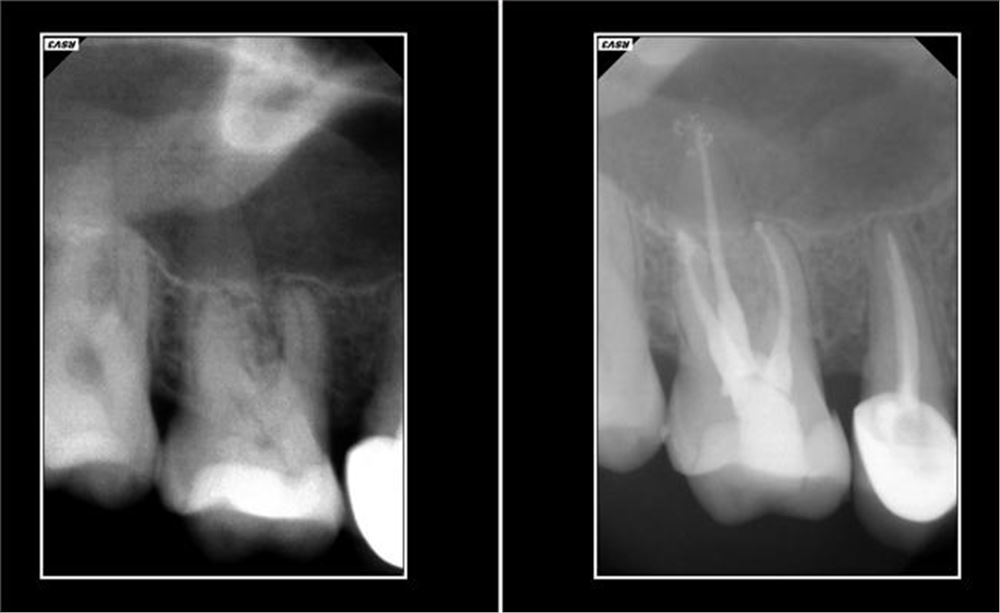

Ohne Behandlung des erkrankten Zahnes können die Bakterien nach Zerstörung der gesamten Zahnpulpa ungehindert in den Kieferknochen eindringen und dort eine Entzündung auslösen, die sich in Form von Aufbißschmerzen bemerkbar machen. Man kann heutzutage die Erkrankung im Röntgenbild als eine dunkle Stelle an der Wurzelspitze erkennen. Durchbricht diese Entzündung den Kieferknochen, kann eine eitrige Schwellung auftreten. Ziel der Wurzelkanalbehandlung ist es, die entzündete oder abgestorbene Pulpa sowie die Bakterien aus der Pulpahöhle zu entfernen und die Wurzelkanäle mit einem gewebefreundlichen Material bakteriendicht abzufüllen. Hierzu verschafft sich der Zahnarzt durch die Zahnkrone einen direkten Zugang zur Pulpa und entfernt den entzündeten oder abgestorbenen Nerv aus dem Zahninneren, falls notwendig mit Betäubung.

Danach wird anhand von Röntgenaufnahmen oder durch ein elektrometrisches Messverfahren die Länge der einzelnen Wurzelkanäle bestimmt.

Abschließend werden die aufbereiteten Wurzelkanäle mit Guttaperchaspitzen (Natur- gummi) gefüllt und durch eine Röntgenaufnahme kontrolliert. Gelegentlich können nach der Behandlung Beschwerden an dem betroffenen Zahn auftreten, meist in Form von Aufbiss- und Berührungsschmerzen, die meist nach einigen Tagen wieder abklingen.

Wundern Sie sich nicht, wenn bei einer Wurzelkanalbehandlung mehrere Röntgenaufnahmen angefertigt werden. Sie sind oft notwendig, um eine exakte Längenbestimmung und – Kontrolle zu erreichen. Durch den Einsatz moderner elektronischer Geräte ist es uns jedoch schon gelungen, die Anzahl notwendiger Aufnahmen zu veringern.